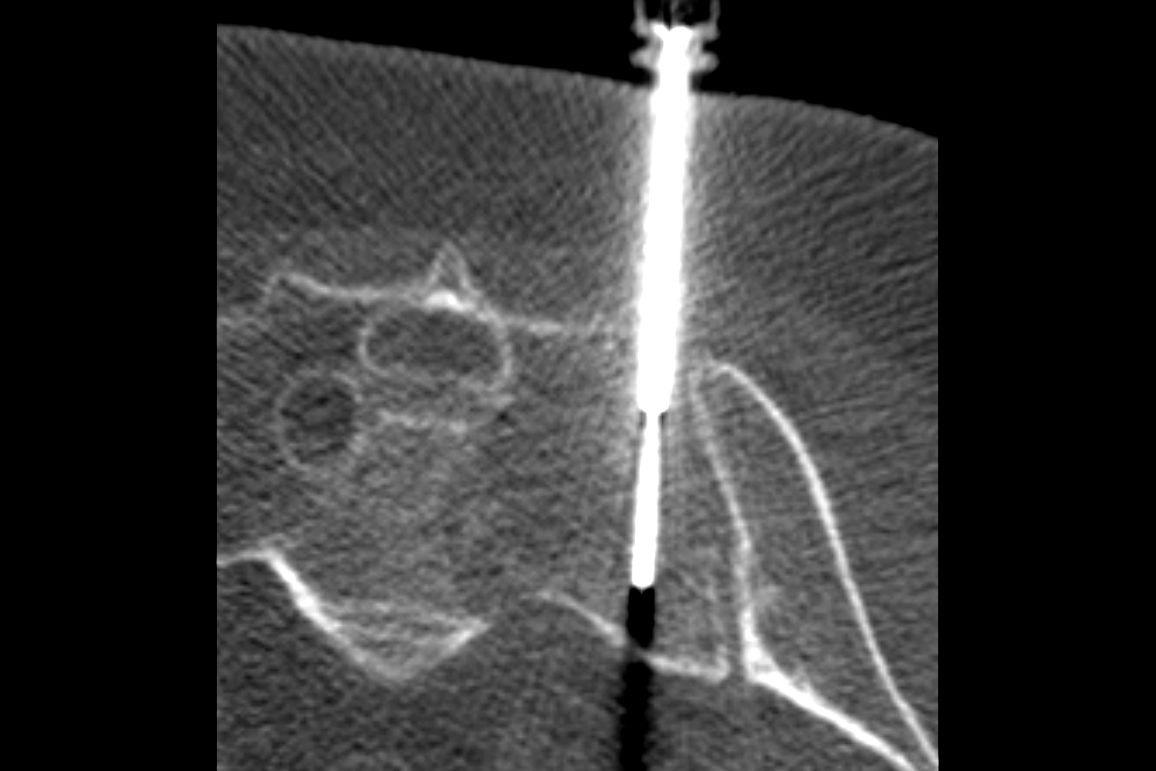

Our program trains all aspects of musculoskeletal radiology, including sports medicine, trauma, arthritis, rheumatology, tumors, and infectious disease. We also offer robust procedural training with ultrasound, spine injection, vertebroplasty, biopsy and ablation. Fellow education is enhanced by numerous interdisciplinary conferences, including arthroscopy correlation, orthopedic oncology, rheumatology, sports medicine and instructive case presentations.

The Musculoskeletal Imaging and Intervention Section at the University of Wisconsin provides imaging interpretation and imaging-guided intervention of the spine and extremities.

The section is composed of internationally renowned experts in all modalities used to image the spine and joints, and skilled professionals in injections to treat back and neck pain. The Musculoskeletal Imaging and Intervention Section also provides rapid, expert confidential consultation of spine, joint and extremity imaging and interventional cases, including complex sports medicine imaging.

Procedures

Spine Procedures